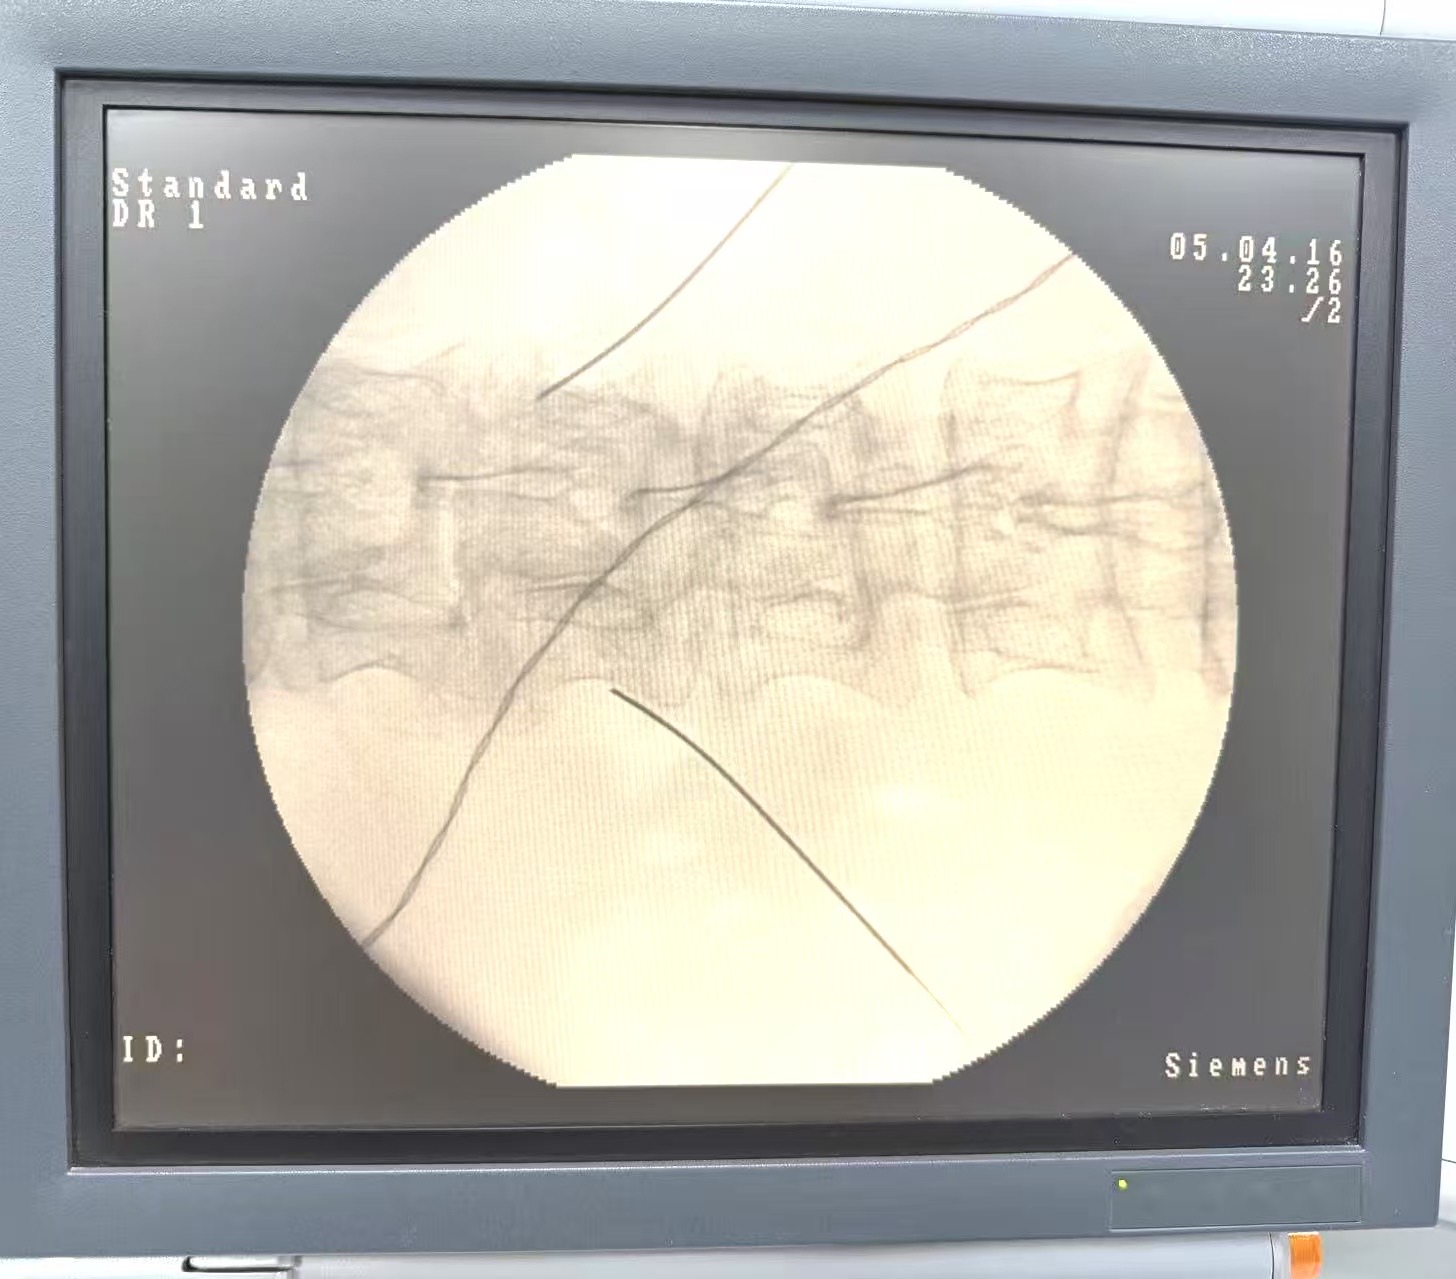

在接诊后,老年内二科在崔巍主任和石静教授的组织下对患者进行了全面评估并与疼痛科展开密切合作。经团队讨论,一方面通过规范药物调整尝试改善症状,并同时由疼痛科每晓鹏主任、申晓东教授、王诗雨医师组成的医疗团队为患者实施了经皮微创介入神经调控术。手术顺利,术后患者腹痛显著缓解,精神状态、进食与休息均有明显改善,生活质量得到实质性提升。